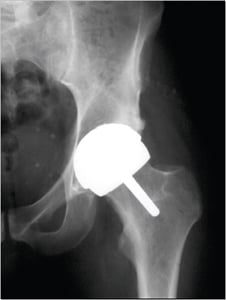

With both traditional hip replacement and surface replacement, the socket is inserted in a similar fashion. The two procedures differ in the way the femur is prepared. Whereas traditional hip replacement involves removing the head and neck of the femur, surface replacement preserves this bone. With a traditional hip replacement, after this bone is removed, a prosthetic ball attached with a stem is inserted within the thigh bone. With a surface replacement, the preserved bone is sculpted to accept a metal cap with a short stem.

Hip resurfacing

Image Courtesy of Smith and Nephew